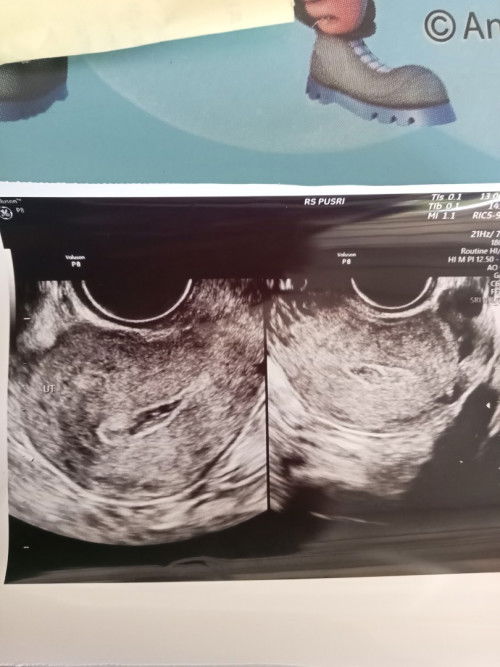

USG transvaginal

Kata dokter SDH tidak berkembang rencana akan dikuret mohon doany ya Bun ๐ข๐